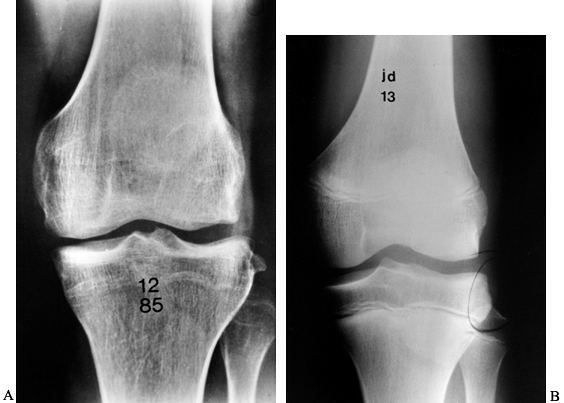

fracture, may be pathognomonic of ACL injury (Fig. 89.1) (121).

Figure 89.1. A:

Anteroposterior radiograph of a skeletally mature right knee with chronic ACL insufficiency. A healed Segond fracture is noted by the bony spur on the lateral tibial plateau’s lateral cortex, proximal to the fibula. B: Anteroposterior radiograph of a skeletally immature individual with a painful traumatic effusion. The x-ray reveals a lateral capsular avulsion, indicative of an injury to the ACL. |